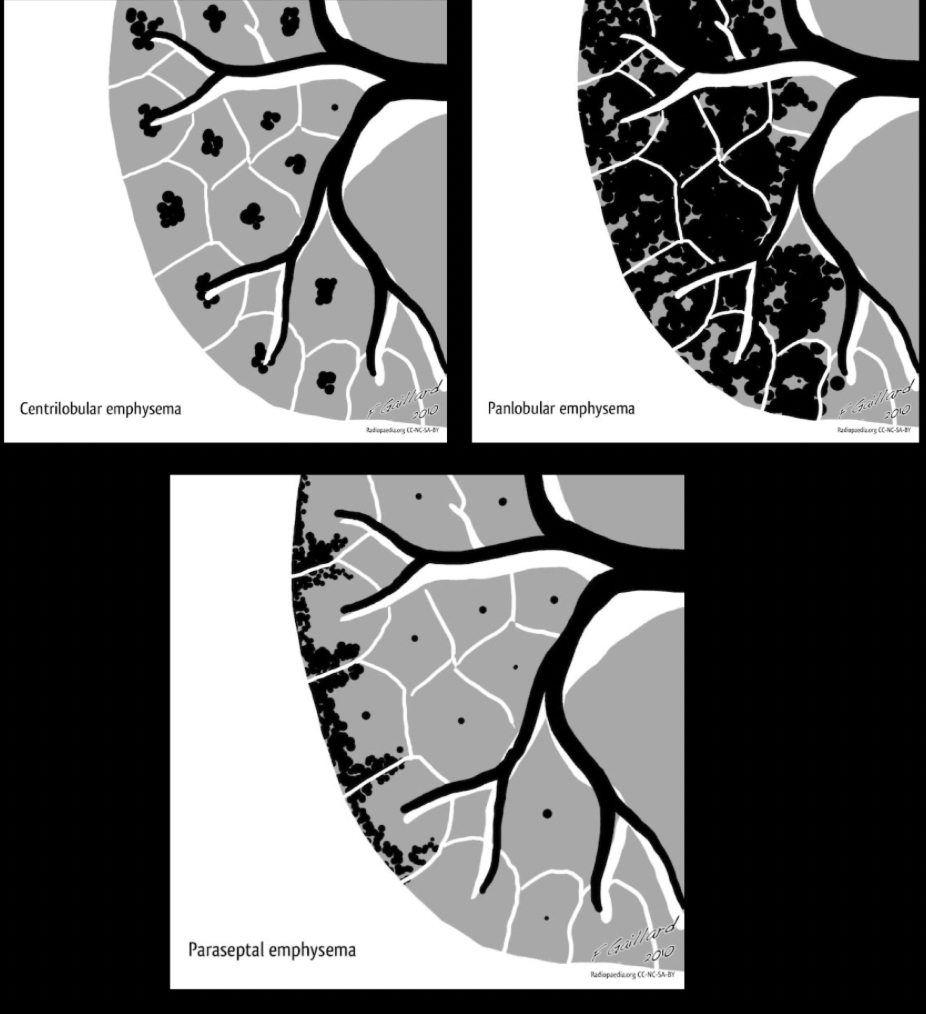

¿Qué nos permite la TC en EPOC?

A

• Distinguir distribución (paraseptal, centrolobulillar y panlobulillar)

• Engrosamiento bronquial

• Atrapamiento del aire

¿Patrones de distribución que tiene el EPOC?